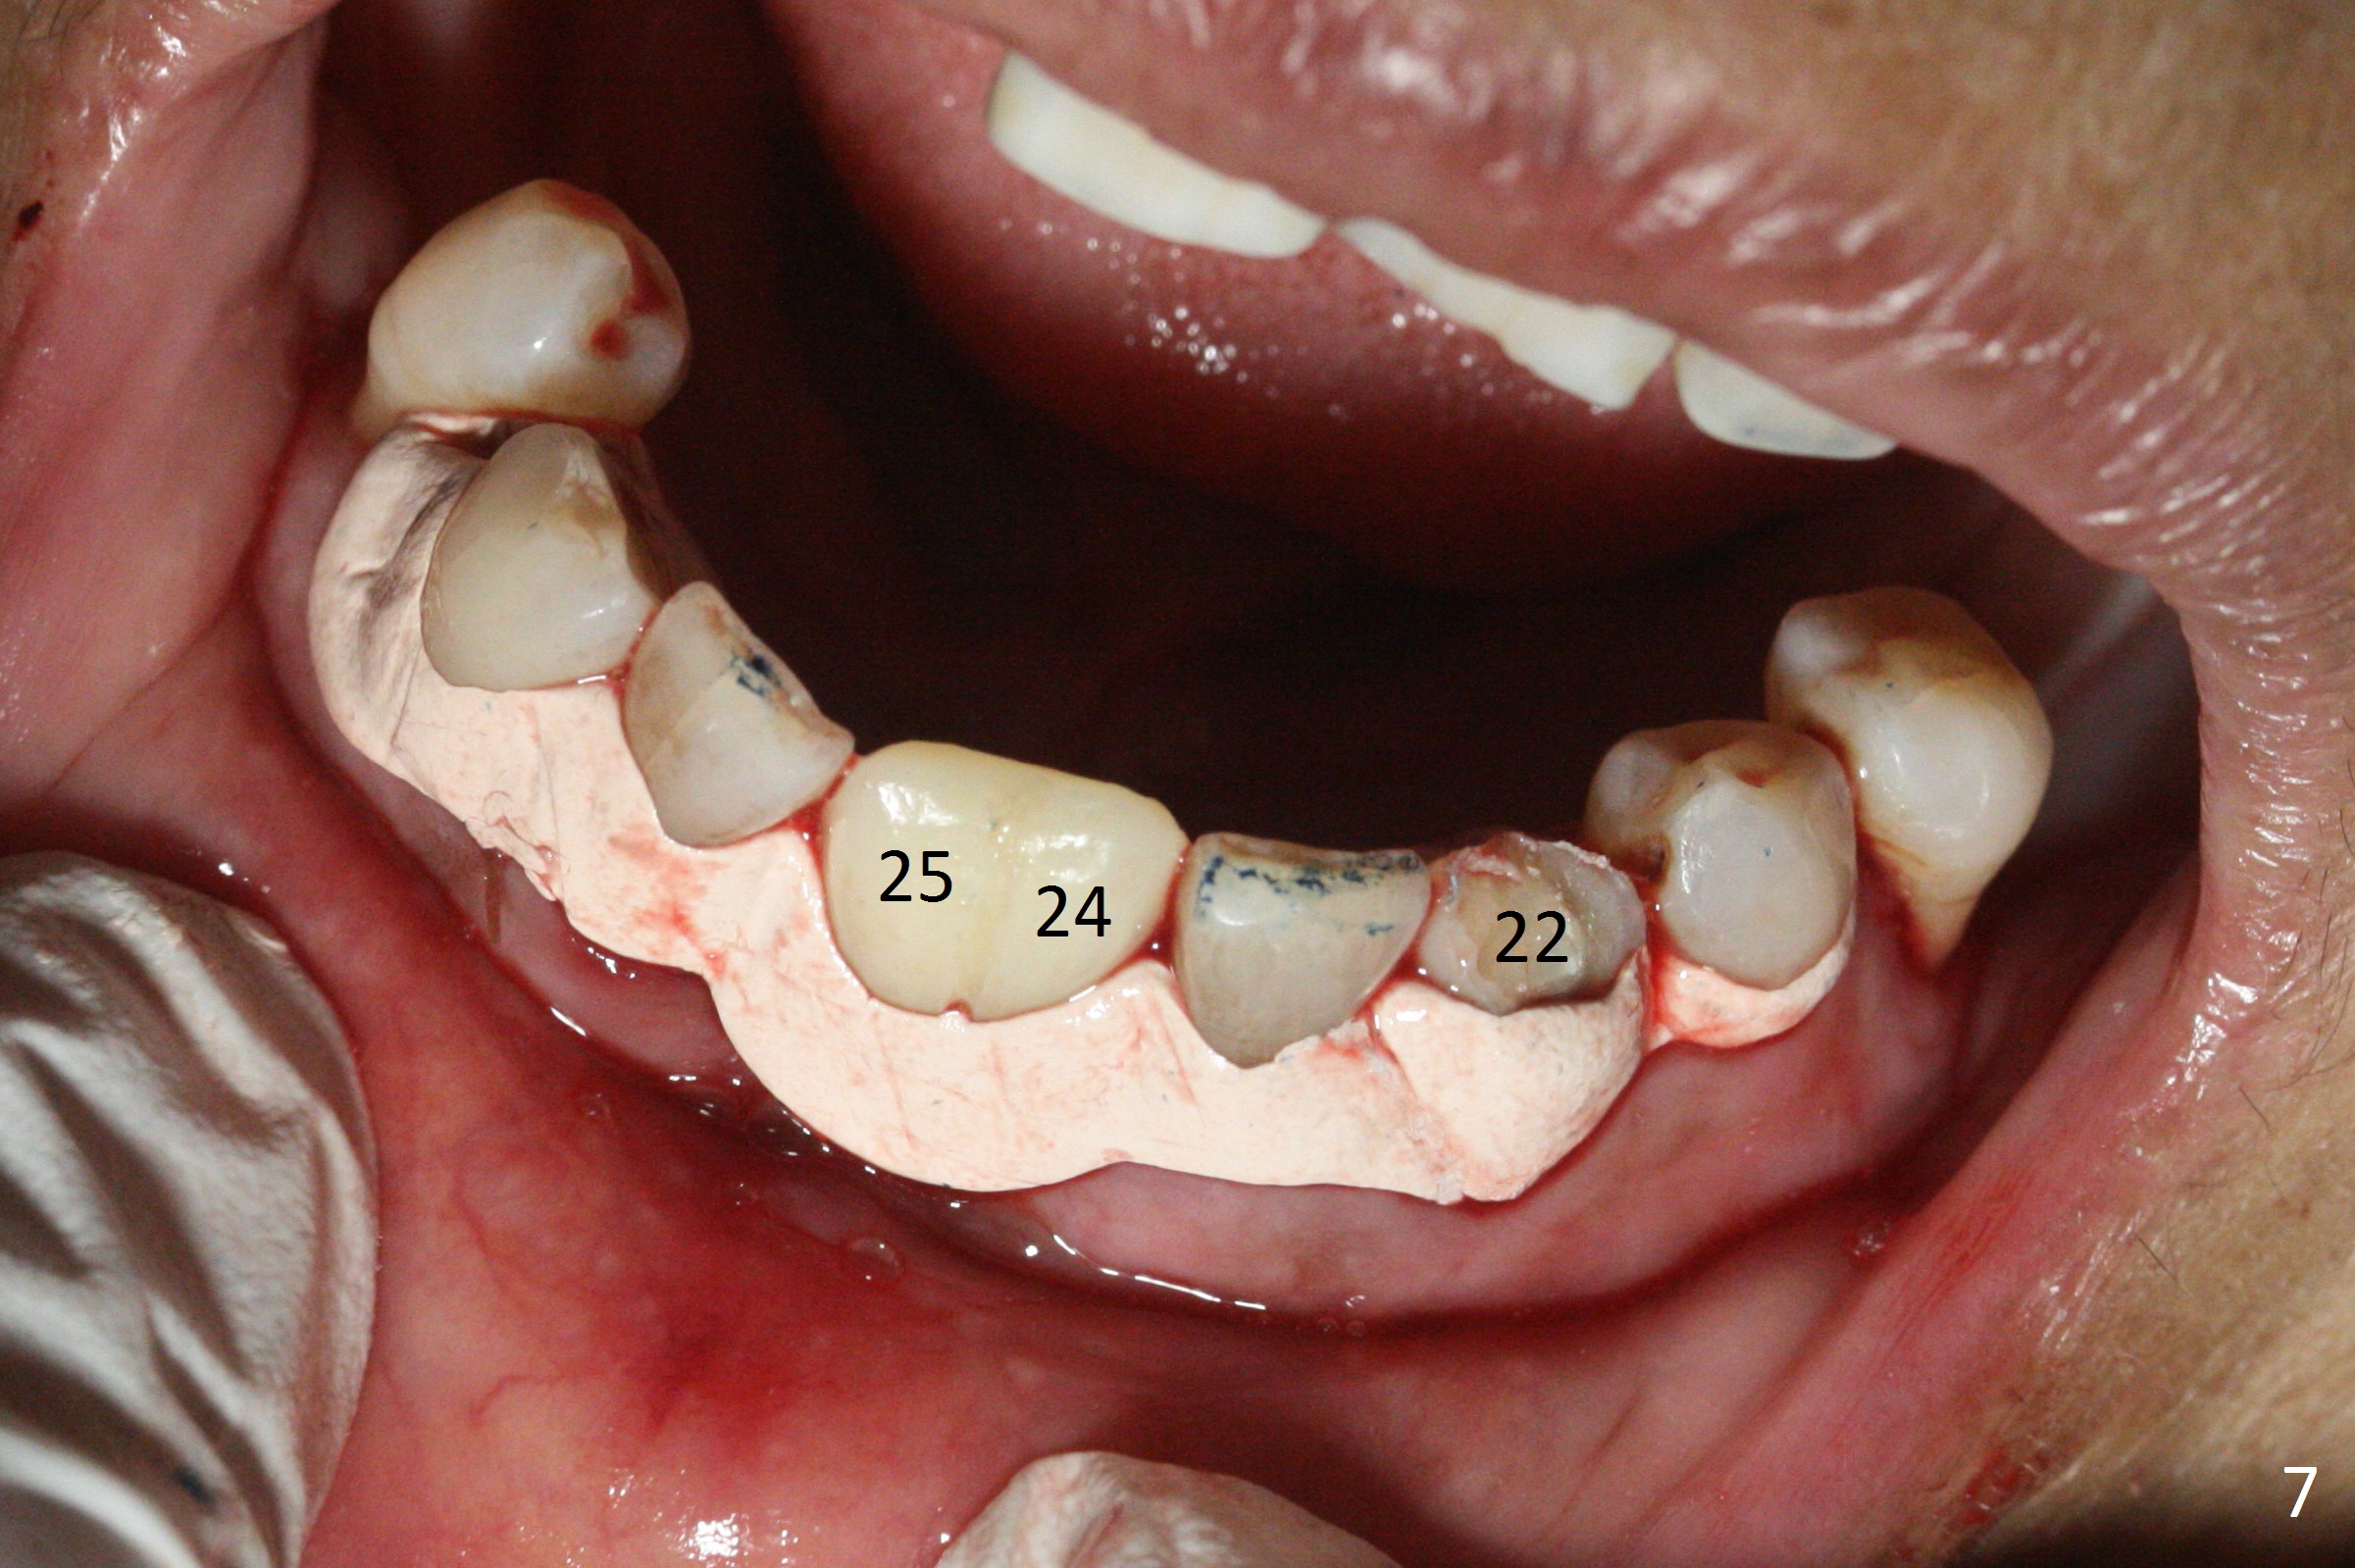

The depth of the osteotomy at #22 is 2-3 mm more than the expected implant length (Fig.2 with 2.7 mm drill in place). The implant at #22 (3.8x18 mm with insertion torque more than 50 Ncm) has clearance from the Incisive Canal and Mental Loop (Fig.3 red dashed line). Allograft with Osteogen is placed around the implants (Fig.4 *) in addition to Osteogen plug (cut in a thin layer) placed against the buccal wall of the socket at #22 (potential leakage). After suturing (Fig.5) and provisional cementation (Fig.6), periodontal dressing is applied (Fig.7). The implants seem to be ready for impression 4 months postop (Fig.8).